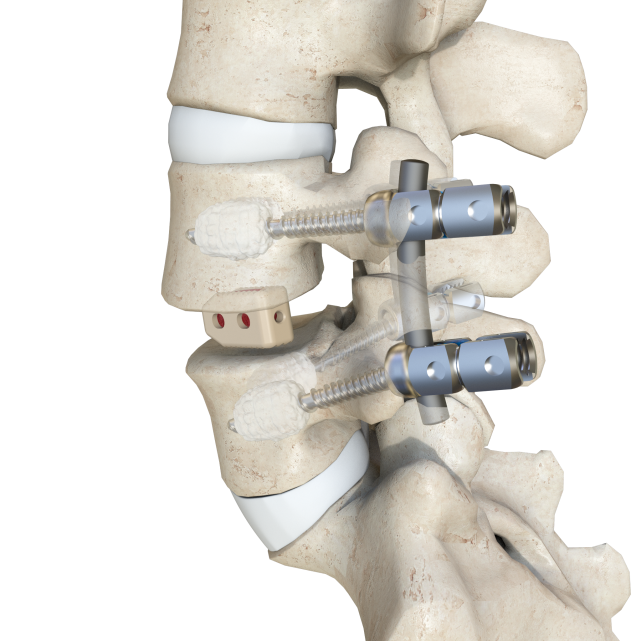

骨水泥強化椎弓根螺釘技術通過骨水泥的彌散,讓骨水泥、螺釘及椎體形成類似樹根狀的復合體,使螺釘和椎體的錨定更加牢固。

德康LEO骨水泥螺釘系統(tǒng)產(chǎn)品介紹

1.安全的側孔設計

最上方側孔距離釘尖15mm,防止出現(xiàn)骨水泥椎管內滲漏風險

2.均布的彌散側孔

3×2側孔120°均布設計,保證骨水泥在椎體前端的均勻彌散

3.良好的流體力學

側孔近端較遠端逐漸減小,減少骨水泥在螺釘中后段的流出量

4.簡單的操作方式

配備專用骨水泥推桿,整體操作更為便捷

5.可靠的卡緊效果

釘桿內沉槽設計,與推桿可靠卡緊,防止骨水泥從配合處的滲漏